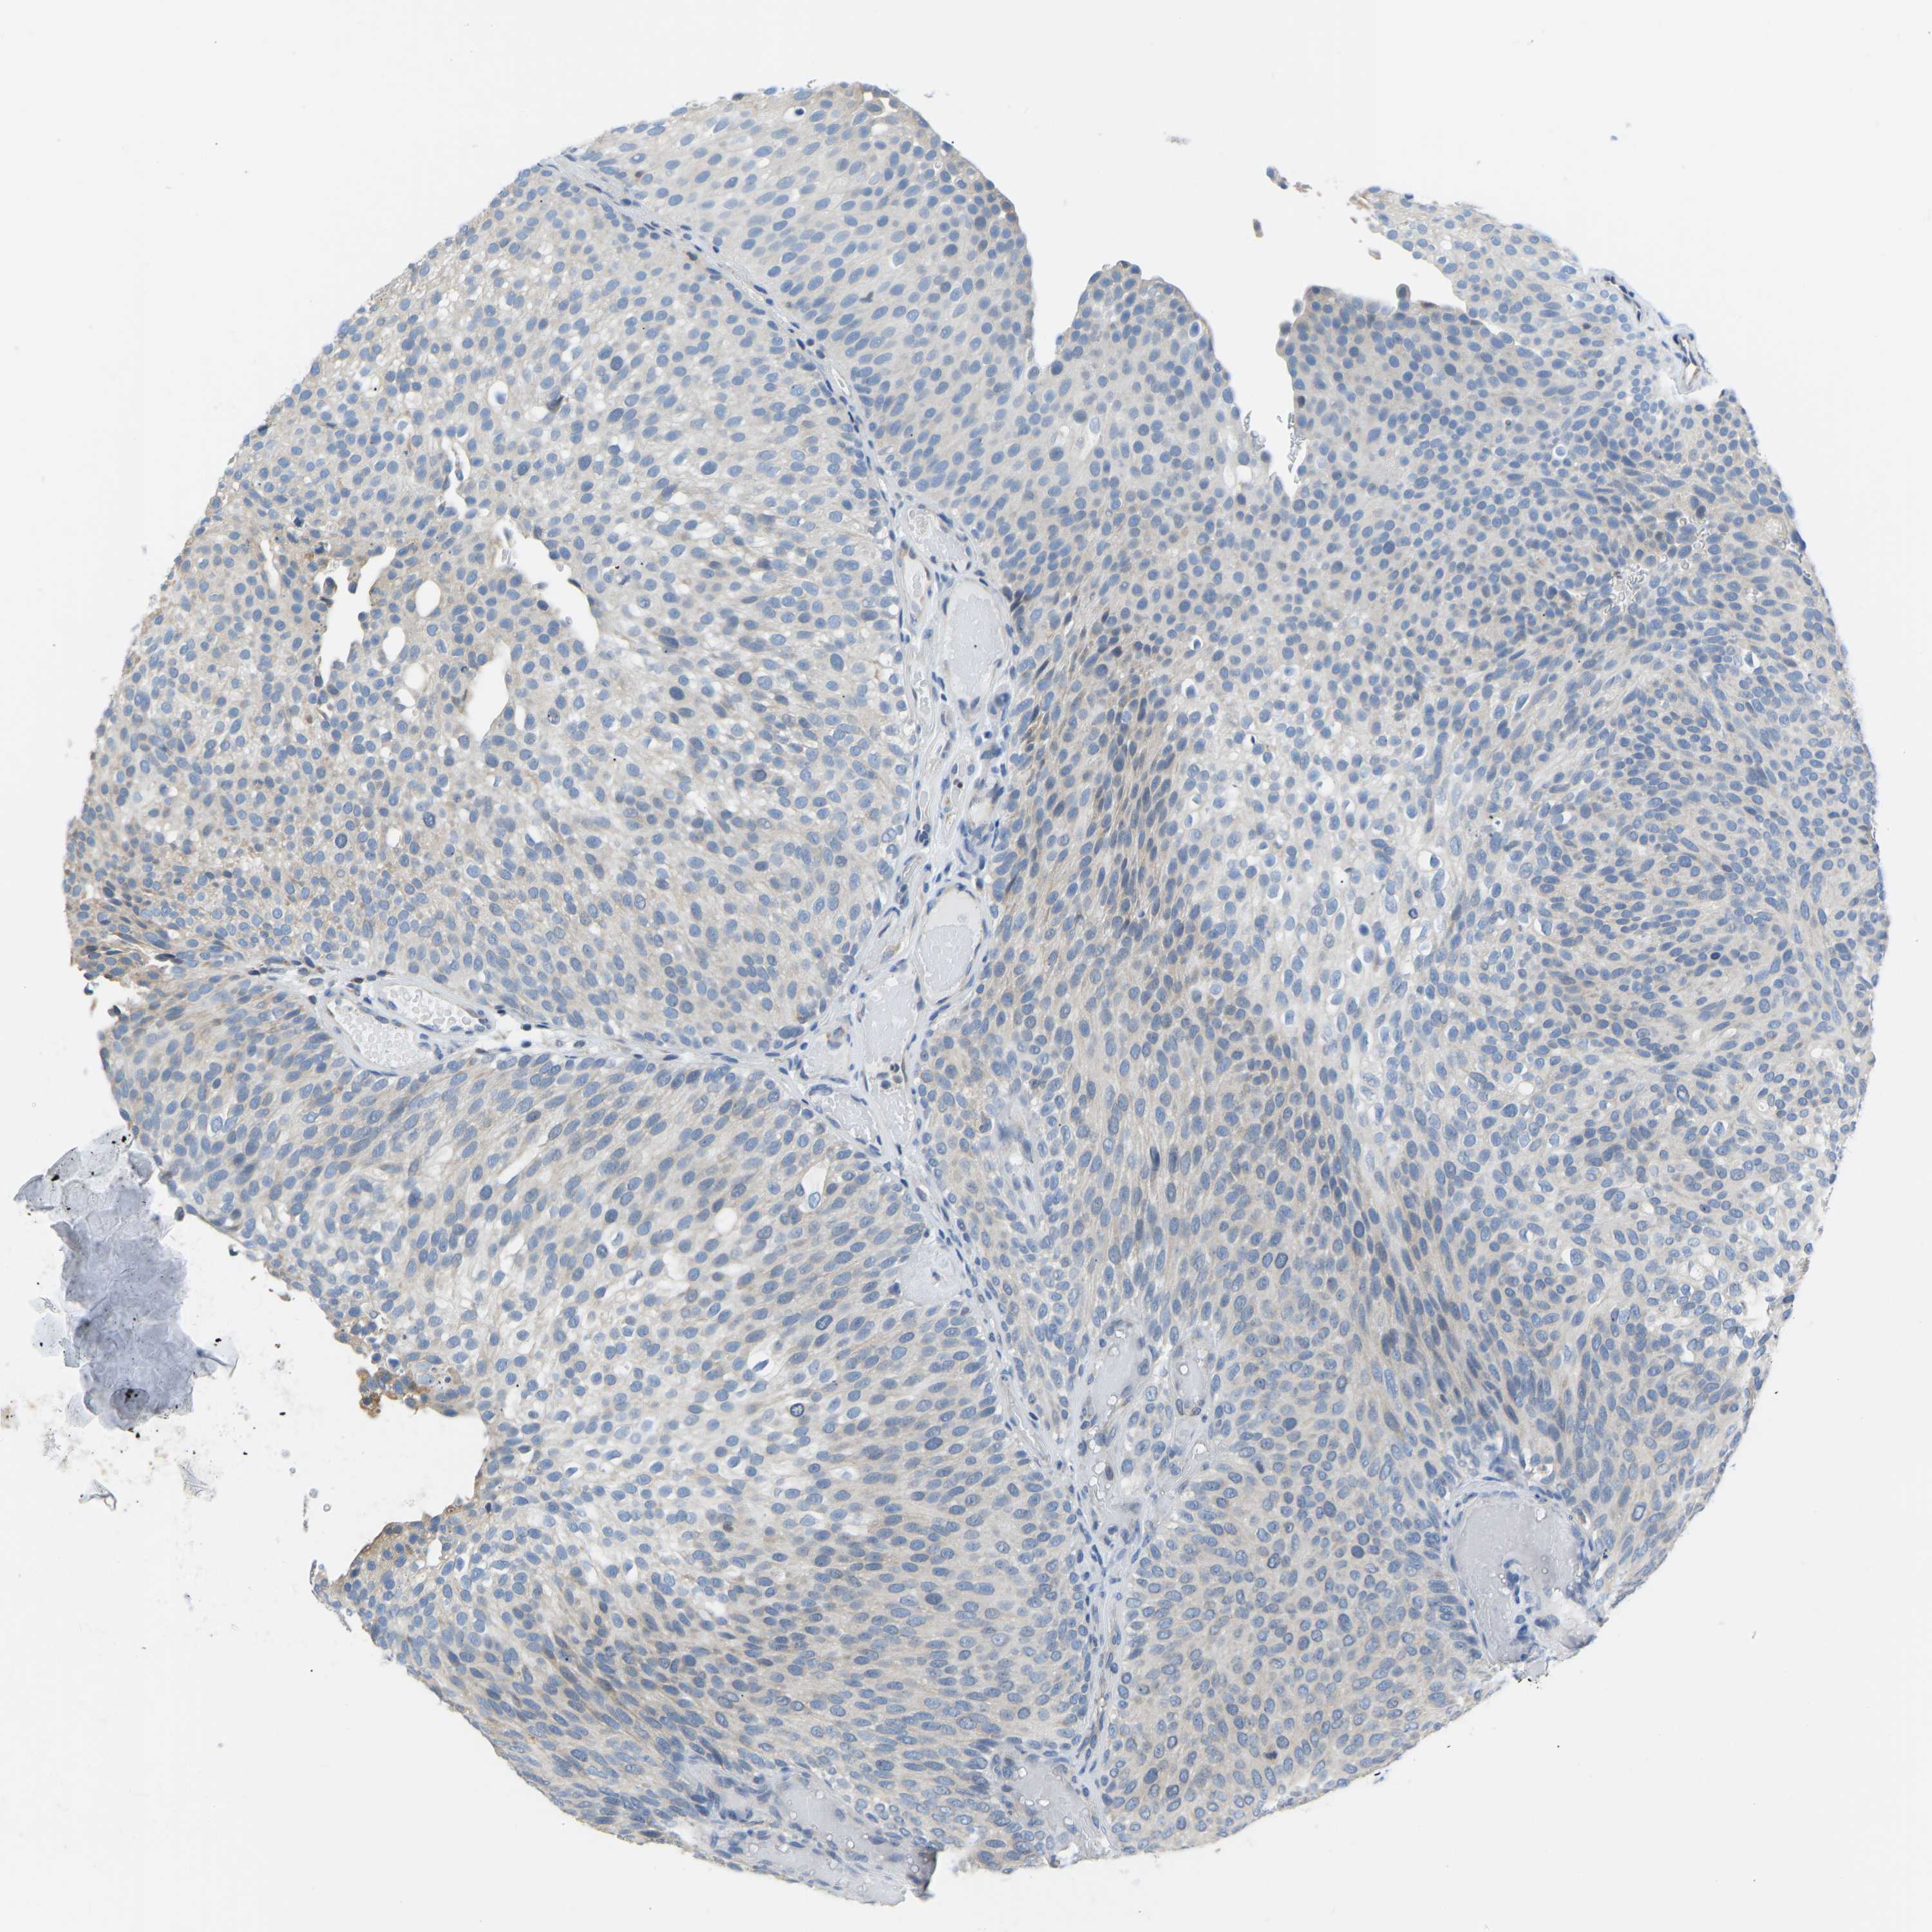

UROTHELIAL CANCER - Protein expressioni

A mouse-over function shows sample information and annotation data. Click on an image to view it in a full screen mode. Samples can be filtered based on level of antibody staining by selecting one or several of the following categories: high, medium, low and not detected. The assay and annotation is described here.

Antibody stainingi

Antibody staining in the annotated cell types in the current human tissue is reported as not detected, low, medium, or high, based on conventional immunohistochemistry profiling in selected tissues. This score is based on the combination of the staining intensity and fraction of stained cells.

Each image is clickable and will lead to virtual microscopy that enables deeper exploration of all samples and also displays staining intensity scores, fraction scores and subcellular localization as well as patient and tissue information for each sample.

Antibody HPA000660

Antibody HPA017929

Staining

High

Medium

Low

Not detected

Intensity

Strong

Moderate

Weak

Negative

Quantity

>75%

75%-25%

<25%

None

Location

Nuclear

Cytoplasmic/membranous

Cytoplasmic/membranous,nuclear

Urothelial carcinoma, High grade

Urothelial carcinoma, Low grade